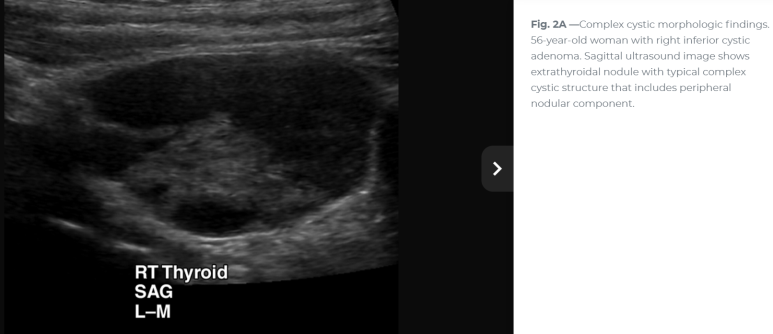

연속 사진으로 내측의 경계가 불규칙하거나 격벽 변화가 있는 모습

확대하면 두꺼운 벽처럼 보이는 부분도 있다. 거꾸로 아래쪽 어두운 곳은 낭성 변화

Imaging included parathyroid ultrasonography, which revealed a cystic appearing mass with septations and mild irregularity (격벽과 불규칙한 내부 경계를 보이는 낭성 종괴)

이번 사례와 같은 위치에 비슷한 모습

For nonfunctional parathyroid cysts, which are usually large simple epithelial cysts, the sonographic features are unlikely to add much specificity to the diagnosis. The primary role of ultrasound in these cases is to guide cyst aspiration for PTH assay to confirm parathyroid origin and potentially for therapeutic intervention. 비기능성 낭종일 경우 초음파의 주된 역할은 부갑상선 기원을 확인하기 위해 PTH assay를 위해 낭종 흡인을 보하는 것이다.